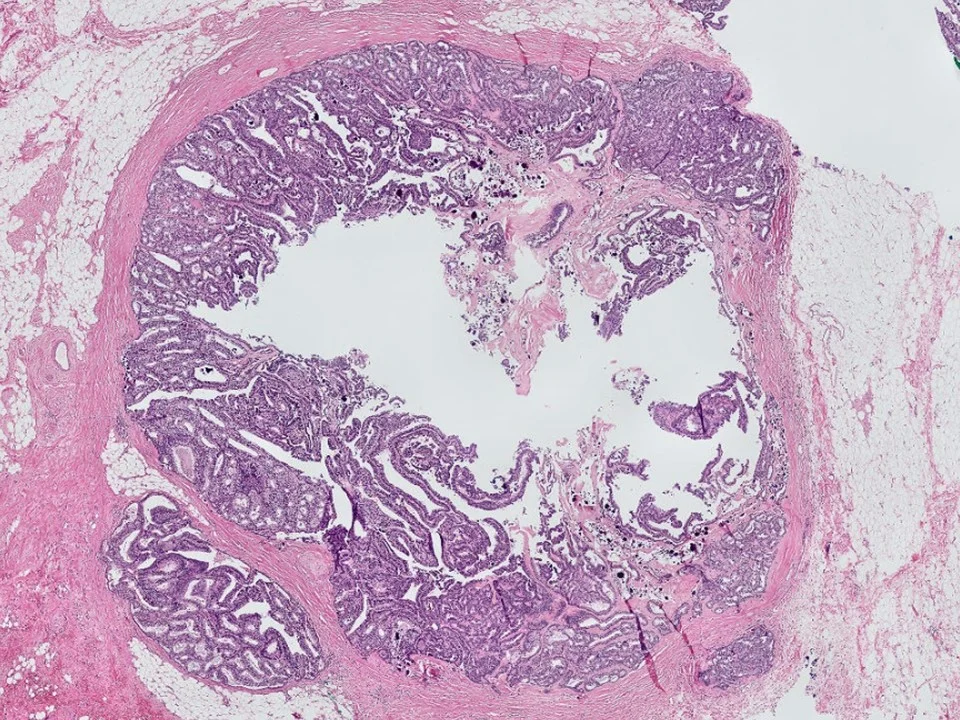

Malignant Phyllodes Tumor

Frond-like projections of cellular stroma covered by epithelium and myopeithelium protruding into epithelial-lined cystic spaces create a leaf-like appearance.

Malignant phyllodes have an infiltrative border (as pictured here), highly cellular stroma, stromal cells with moderate to marked nuclear pleomorphism, and prominent mitotic activity (>/= 10 mits per 10 HPF)